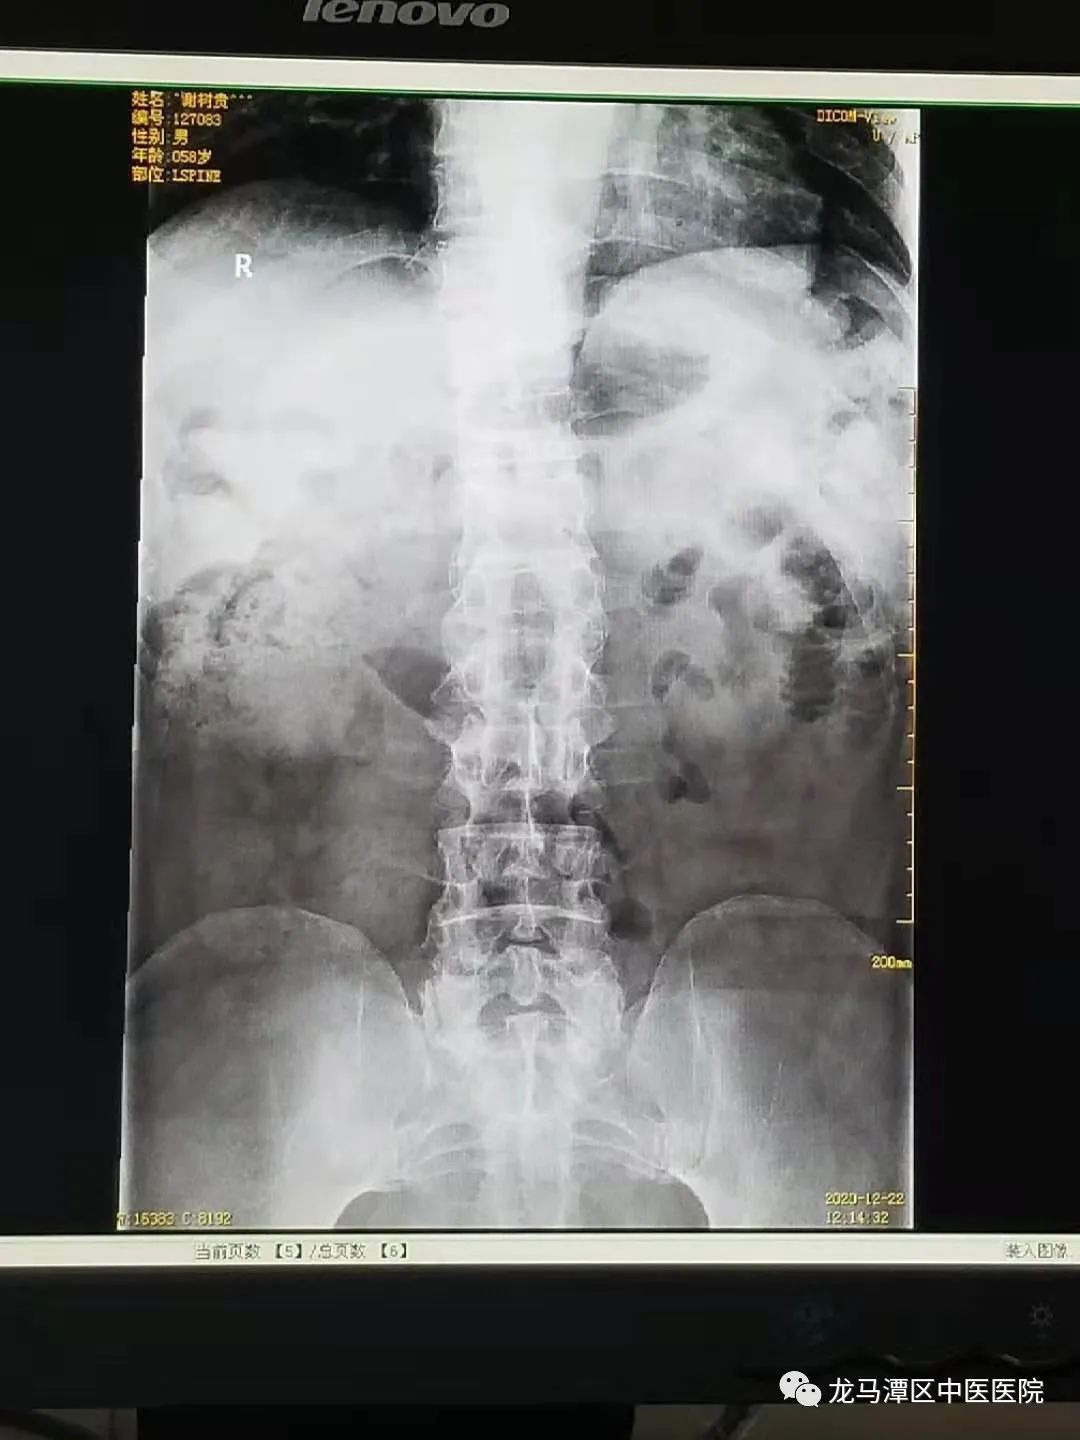

手术前

患者于4+年前无明显诱因出现颈肩部酸痛,到当地县医院就诊,经CT检查,诊断为颈椎病,在当地卫生院及个体医生等处理疗,症状有所减轻。1+年前患者出现右上肢发麻、双下肢无力,经反复在外就诊治疗无好转,于2020年12月22日入住我院骨伤一科。患者曾于30+年前因外伤致“腰椎骨折”行手术治疗。

入院时查体:颈部无明显肿胀,颈椎棘突无明显肿胀、压痛,颈部可屈伸旋转活动,脊柱胸腰段后凸畸形,腰背部有一长约12cm的手术疤痕,无明显肿胀、压痛,胸腰椎棘突无明显压痛,T12-L2椎体棘突缺如。双小腿肌肉萎缩,双下肢3级肌力,双膝关节以下痛触觉不敏感,双膝关节以上痛触觉敏感,双踝关节及双足趾不能活动,双下肢血循可。右上肢握力减退,右上肢痛触觉减退,左上肢握力无明显减退,左上肢痛触觉稍减退,双上肢血循可。

结合西南医科大附属医院DR、CT及MR等检查提示,入院诊断:1、T12-L2椎体陈旧性压缩性骨折伴双下肢不全性瘫痪;2、脊髓空洞症;3、颈椎病;4、腰椎退行性变伴失稳